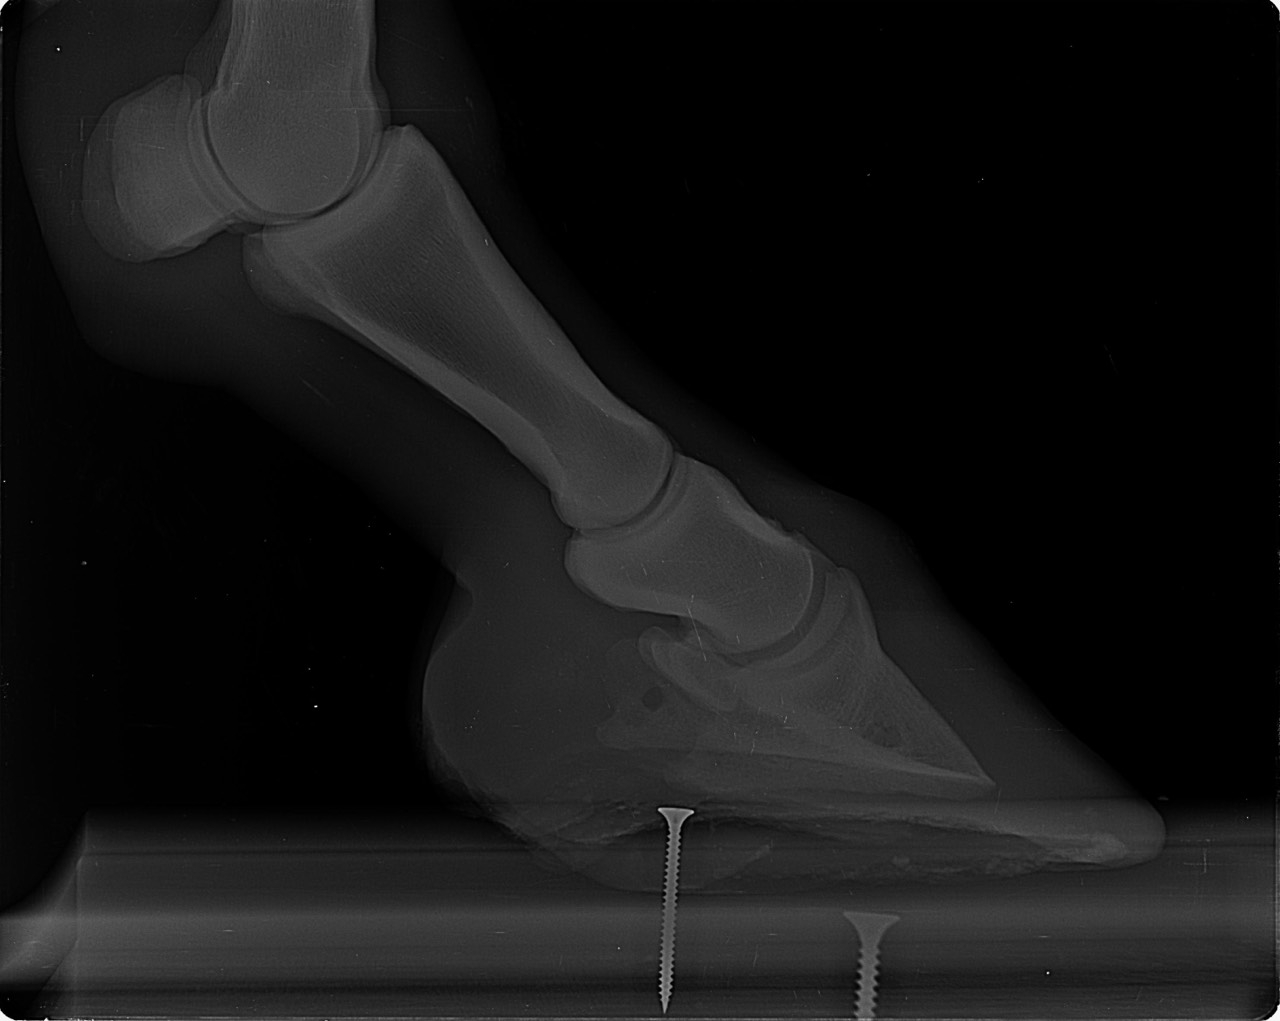

| Dire merci | Je fais un sujet à part pour donner des nouvelles ![]() J’ai fait passer un autre véto pour un 2ème avis. Au début il pensait à un abcès très profond, emplacement détecté avec la pince à sonder. Il a ensuite fait des radios : si j’ai bien compris, la 3ème phalange appuie sur la sole Il y a également de l’arthrose ... Le traitement pour le moment : anti inflammatoires et hipposandales en attendant de pouvoir referrer, et changer de maréchal ferrant. Apparemment il existerait un traitement au laser, le véto va se renseigner. Cody a fait une fourbure l’année dernière, des radios ont été faites à ce moment. J’ai aussi refait des radios de contrôle cette année, il restait une légère bascule de P3. |

| Dire merci | Radios de mai 2023![]() ![]() Radios de juillet 2023 ![]() ![]() Radios d'août 2024 ![]() ![]() |